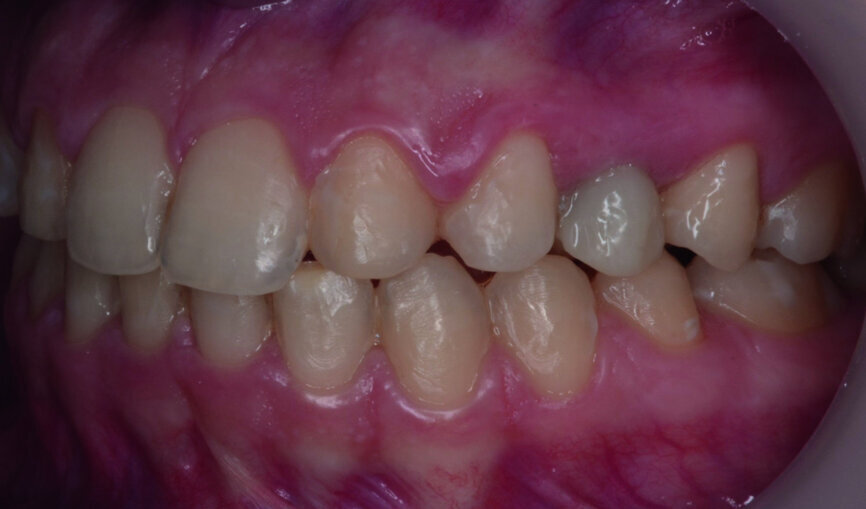

Then occlusal analysis (Figs. 11–21) was performed:

- Skeletal Class III (Fig. 17).

- Dental Class I.

- Maxillary hypoplasia with lower arch dental compensations.

- Insuficient overbite and overjet.

- Upper spacing due to the laterals agenesis (Fig. 18).